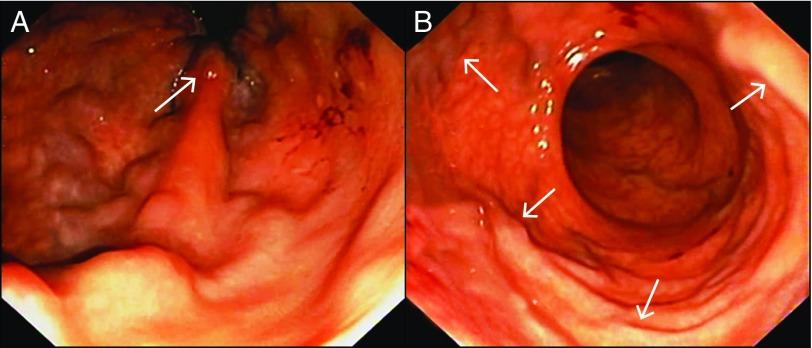

Rectal variceal bleeding, though rare, can pose significant morbidity and mortality in the wake of treatment failure. Conventional treatment utilizing endoscopic glue injection might not be feasible in all cases due to poor visualization and inadvertent missing of variceal source of bleed. Endoscopic ultrasound (EUS)-guided rectal variceal management is a promising and effective modality. We provide real-time images and a video of EUS-guided precision management of rectal variceal bleed using coiling and glue in a cirrhotic.

直肠静脉曲张出血虽罕见,但治疗失败后可导致严重的发病率和死亡率。由于视野不佳和无意中遗漏静脉曲张出血源,利用内镜下注射胶水的传统治疗在所有病例中可能都不可行。内镜超声(EUS)引导下的直肠静脉曲张治疗是一种有前景且有效的方法。我们提供了在一名肝硬化患者中使用线圈和胶水进行EUS引导下直肠静脉曲张出血精准治疗的实时图像和视频。